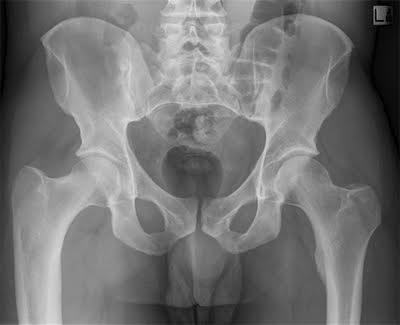

X-ray technology is used to examine many parts of the body.

Bones

- Fractures and infections. In most cases, fractures and infections in bones and teeth show up clearly on X-rays.

- Arthritis. X-rays of your joints can reveal evidence of arthritis. X-rays taken over the years can help your doctor determine if your arthritis is worsening.

- Osteoporosis. Special types of X-ray tests can measure the density of your bones.

- Bone cancer. X-rays can also reveal tumors in your bones.